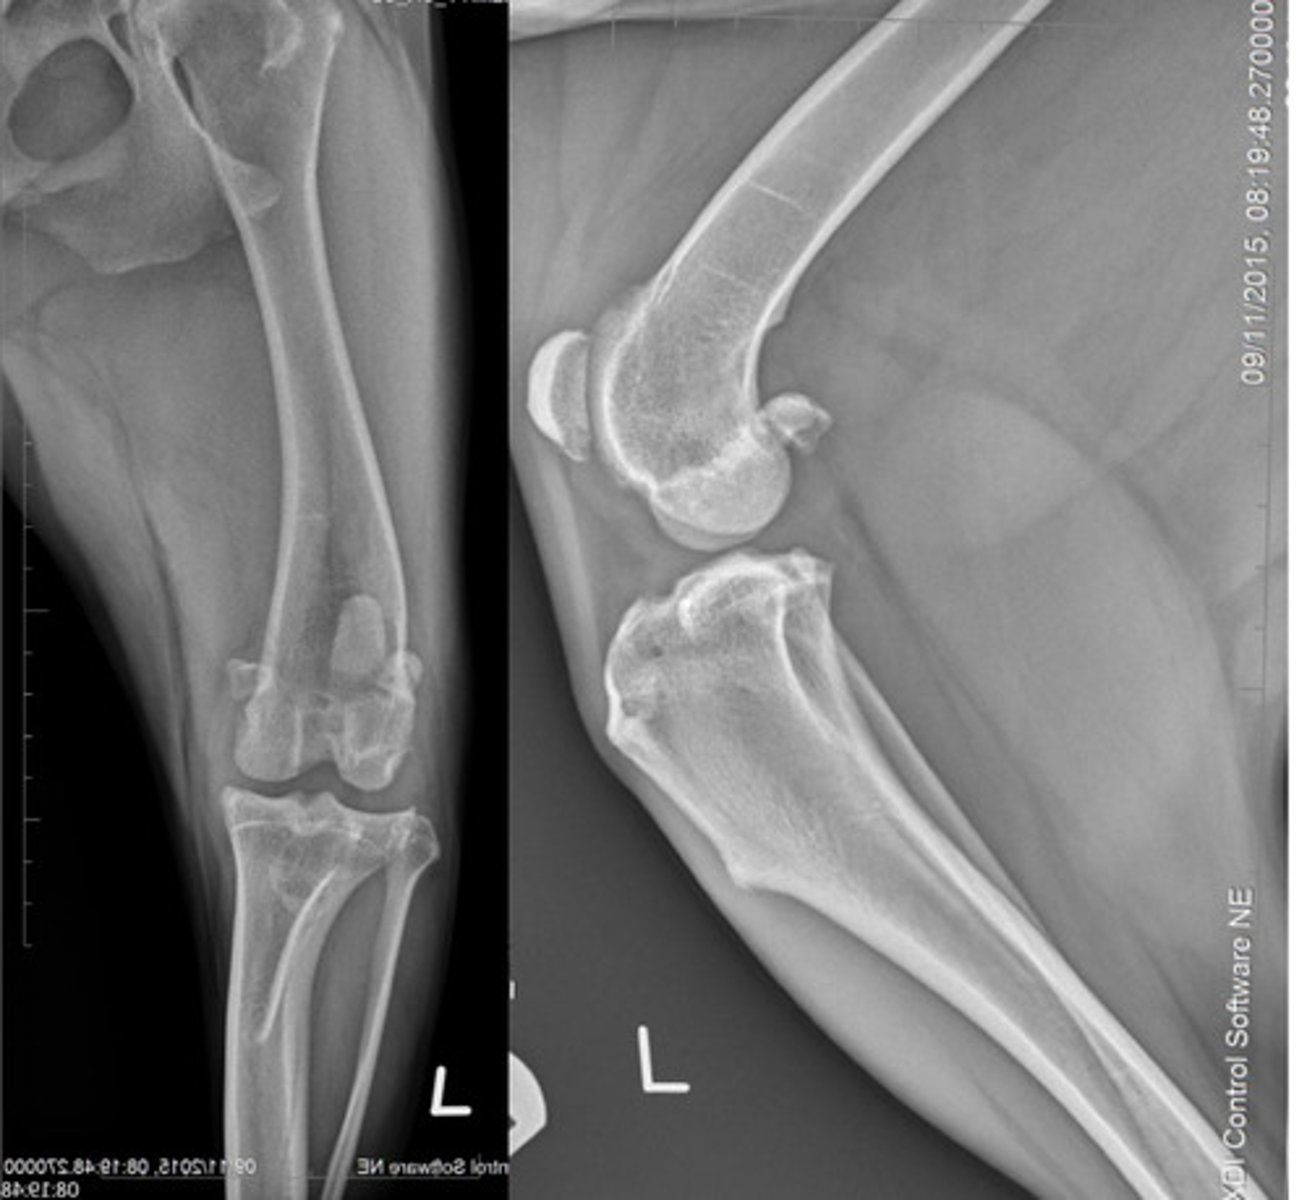

What does this patient have?

Osteoarthritis